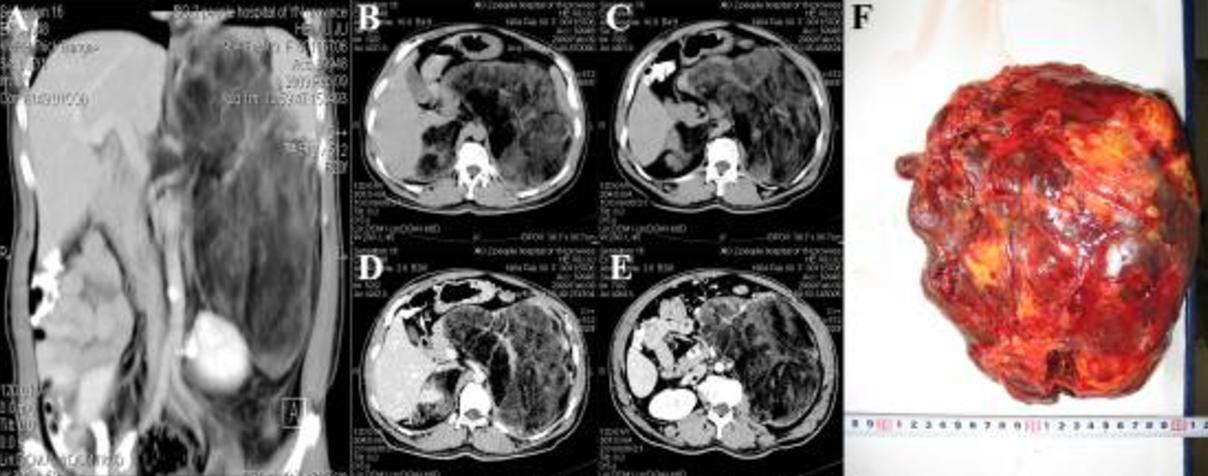

腹部CT检查显示左侧腹膜后间隙有一巨大的混合密度病变(18cm×15cm),包括许多不规则的脂肪密度影。肿物的上边界位于横膈膜下方,下边界位于髂嵴水平面。胰腺、胃和脾脏都被挤压移位,左肾被挤压到骨盆中。右肾上方可见边界清晰的8cm×4cm混合密度影。行增强CT时,左侧腹膜后肿物的实质部分显示出增强,似乎被包裹(图1A–E)。

图1 患者的CT和大体标本。(A) 左侧腹膜后肿物巨大,左肾受压下移。增强扫描未发现增强。(B,C)CT平扫显示双侧不均匀密度肿物。(D,E)双侧肾上腺增强CT表现。(F) 左肾上腺巨大肿物的术中大体标本